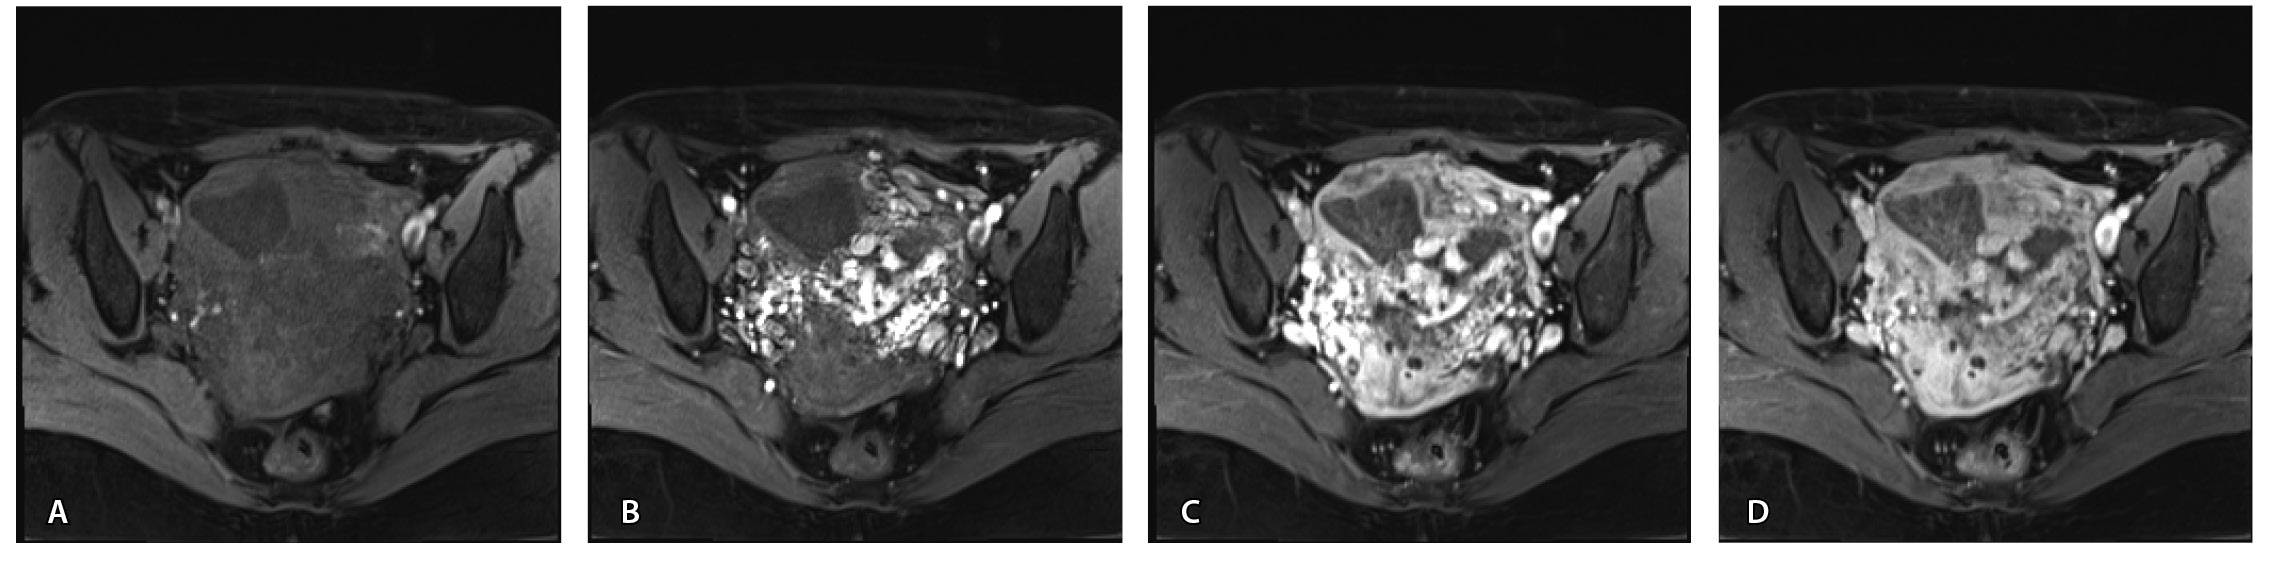

Пациентке выполнено МРТ-исследование на МР-томографе Siemens MAGNETOM Verio с индукцией магнитного поля 3T, с использованием стандартных катушек, в режимах Т1-взвешенного изображения (ВИ), Т2-ВИ, Т2-FS, FIESTA, DWI с получением изображений в сагиттальной, корональной и аксиальной плоскостях, динамическое внутривенное контрастирование (гадопентетовая кислота 0,2 мл/кг массы тела). Матка увеличена в размерах, с признаками снижения зональной дифференциации стенок, усиленным сосудистым компонентом, полость матки расширена с наличием примеси геморрагического содержимого, неравномерным утолщением эндометрия и пристеночными компонентами слизистой. В нижнем маточном сегменте определяется несостоятельный рубец от кесарева сечения, с наличием участка резко истонченной пролабирующей стенки матки слева и наличием дополнительного образования неоднородного сигнала, суммарно до 4,0 × 2,3 × 3,2 см, представленного фрагментами мягкотканного хориона (изоинтенсивного на Т2-ВИ), достигающего серозного покрова матки, и патологического сосудистого компонента в виде расширенных полнокровных сосудов, зон неоангиогенеза (рис. 1). На DWI признаков ограничения диффузии не определялось.

Рис. 1. Остатки вросшего хориона в несостоятельный рубец от кесарева сечения. Магнитно-резонансная томограмма, Т2-взвешенное изображение в сагиттальной (А), корональной (Б), аксиальной (В) плоскостях. Признаки наличия в проекции несостоятельного рубца от кесарева сечения фрагментов ткани вросшего хориона изоинтенсивного сигнала (отмечен звездочкой), с распространением до серозного покрова матки. Стрелками указаны гипоинтенсивные сосуды, зоны неоангиогенеза, артериовенозные сосудистые коллатерали

По наружной поверхности нижнего маточного сегмента и в параметрии определяется наличие полнокровной сосудистой сети с артериовенозными анастомозами. При контрастировании визуализируются фрагментарные участки гиперваскулярного накопления контраста вышеописанным образованием в рубцовой нише, а также определяется наличие артериовенозной сосудистой мальформации (рис. 2).